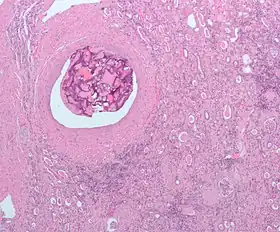

Foreign bodies in the peritoneum eventually become contained in a foreign body granuloma. In the extremely rare case of retained ectopic pregnancy, this forms a lithopedion, which involves the fetus being too large to be reabsorbed, and is calcified[13] as a means of shielding the surrounding tissue from infection.